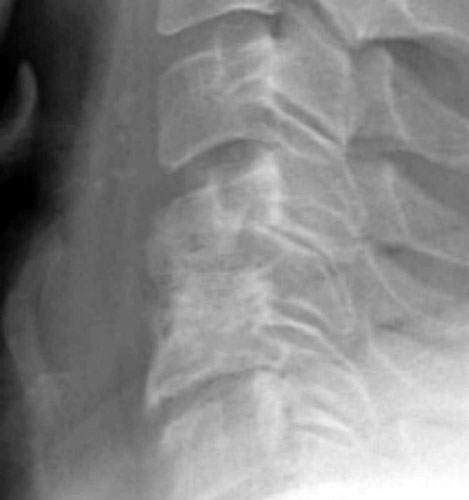

Initial post-operative films show bone graft intact, with mildly prominent pervertebral soft tissues, as expected in the immediate post-operative period.